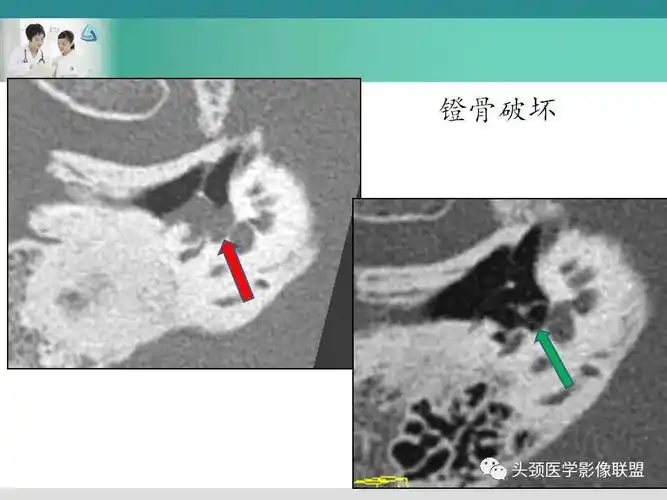

【病例】右侧中耳乳突炎(胆脂瘤型)1例ct影像表现

中耳解剖及慢性中耳乳突炎影像诊断与鉴别